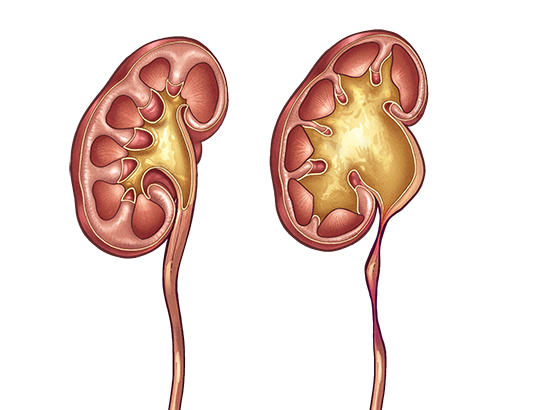

Интраренальная лоханка: рентгеновские снимки и примеры

Раздел: Фотоэссе